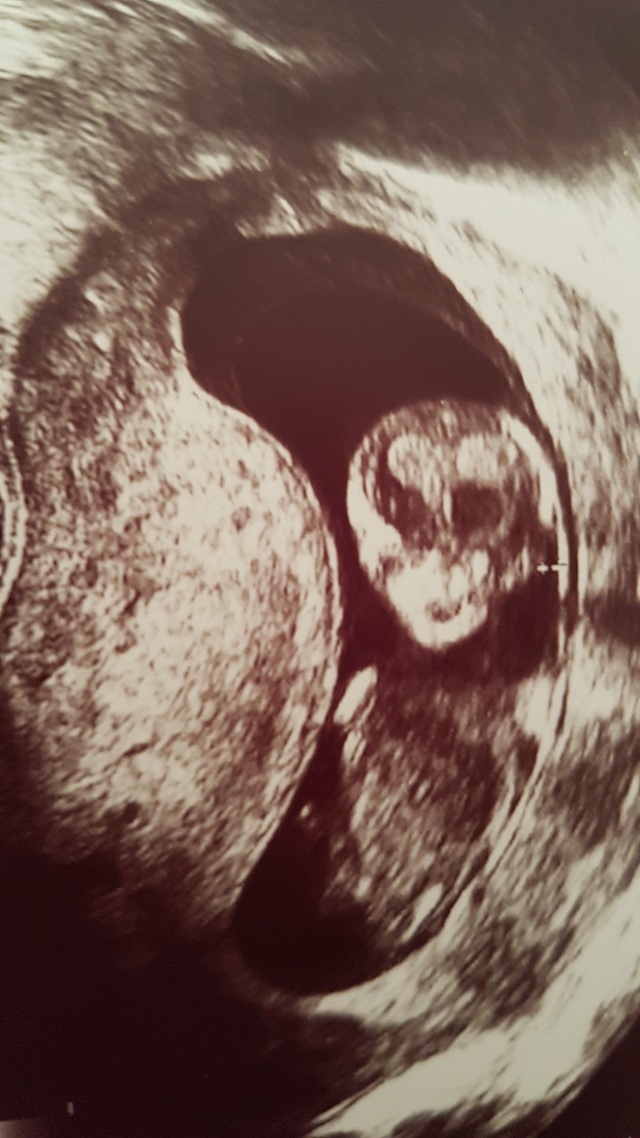

15週1日(15w1d・女の子)|トスカチーナ さん(24歳)

エコー写真撮影時のエピソード:

この頃はつわりが酷くて、毎日ゼリー生活をしてました。とっても辛かったのを今でも覚えています。でも栄養を取らなくては

と、食べれる時にタンパク質とかビタミン摂取をして、サプリも飲んでたりしました。健診の待ち時間ですら、椅子に座ってるだけでも辛かったなぁ。そんな中一ヶ月ぶりの健診でエコーをみて先生が赤ちゃんがこっちを見ているよ!写真好きなのかな?と言って見せてくれたエコー写真がこれでした。ちゃんと顔が見れるのは初めての事だったのでこっち見てるなんて嬉しい!と思っていましたが、エコー写真を見た第一声はえ、怖っっ!でした笑。宇宙から来たのか?!うちの子は宇宙人なのか?!とびっくりしました笑主人も、怖い!え、怖い!と、この写真を見て顔をしかめていましたが、今となっては笑い話になるエコー写真です。でもその時はほんと怖かった!!笑怖いとか言ってごめんねベビちゃん!